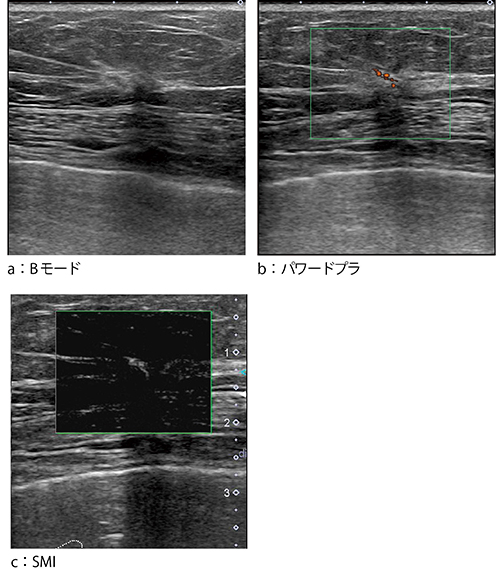

●症例3:非浸潤性乳管癌(DCIS)(64歳)

症例3は,マンモグラフィ検診にて左乳房にdistortionを指摘された。Bモードでも同様にdistortionが確認できたが,腫瘤かどうかは不明確であった(図5 a)。パワードプラでは,血流が点在する様子がわずかに見られるのみであったが(図5 b),SMIでは中を貫くような血流が描出された(図5 c)。本症例は,最終的には吸引式組織生検(VAB)にてDCISと診断された。

図5 症例3:非浸潤性乳管癌(DCIS)(64歳)